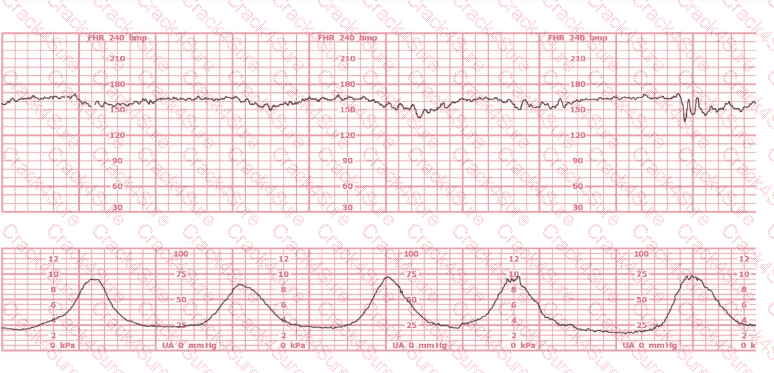

A woman (G1, P0) at 41-weeks gestation presents to OB triage to rule out labor. Her cervical exam is 1 cm/50%/-2. Membranes are intact. She would like to go home if not in labor. Based on this tracing, which represents the last two hours, the best approach is: